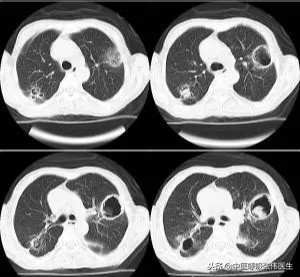

肺曲霉菌球是寄生型肺曲霉菌病的常见表现,多出现于支气管扩张或空洞型肺结核患者中。临床表现为间断反复咯血,伴有咳嗽、胸痛,少数可出现致命性大咯血。典型的影像学表现为在厚壁或者薄壁空洞内可见边缘明确的均匀结节,伴有空气新月征。

IPA是肺曲霉菌病中最常见且危害最严重的类型,病死率最高。常常累及肺组织以外的器官或形成曲霉菌败血症。常发生在免疫抑制的病患中,血液系统疾患及骨髓移植是侵袭性曲霉菌病的最危险因素。在机体免疫功能正常的人群中很少发病。临床表现非特异性,主要表现为发热、干咳、咯血、胸痛等,病变广泛时可出现呼吸困难。IPA早期CT可表现为特征性的晕轮征,图像上表现为围绕结节的密度高于肺实质但低于结节的环形带,不典型时表现为结节边缘模糊不清。